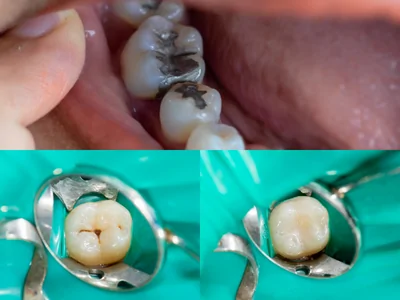

Tooth fillings vary in longevity, strength, cost, color, length of procedure time and patient satisfaction. Amalgam or silver fillings have been the most popular in the world for many decades but the tooth colored resin fillings are gaining more popularity and acceptability. Gold fillings are technique sensitive and the color may not be agreeable to everybody. Tooth colored porcelain inlays or onlays are excellent restorative choices for teeth needing moderately large restorations that are not really in need of a full coverage crown.

Four Alternatives for Posterior Restorations (cavity fillings on back teeth)

Some restorative materials are weaker than natural tooth like silver, resin and inlays. Onlays, both gold and ceramic are stronger than natural tooth.

Silver Fillings

Resin Fillings

Inlay or onlays